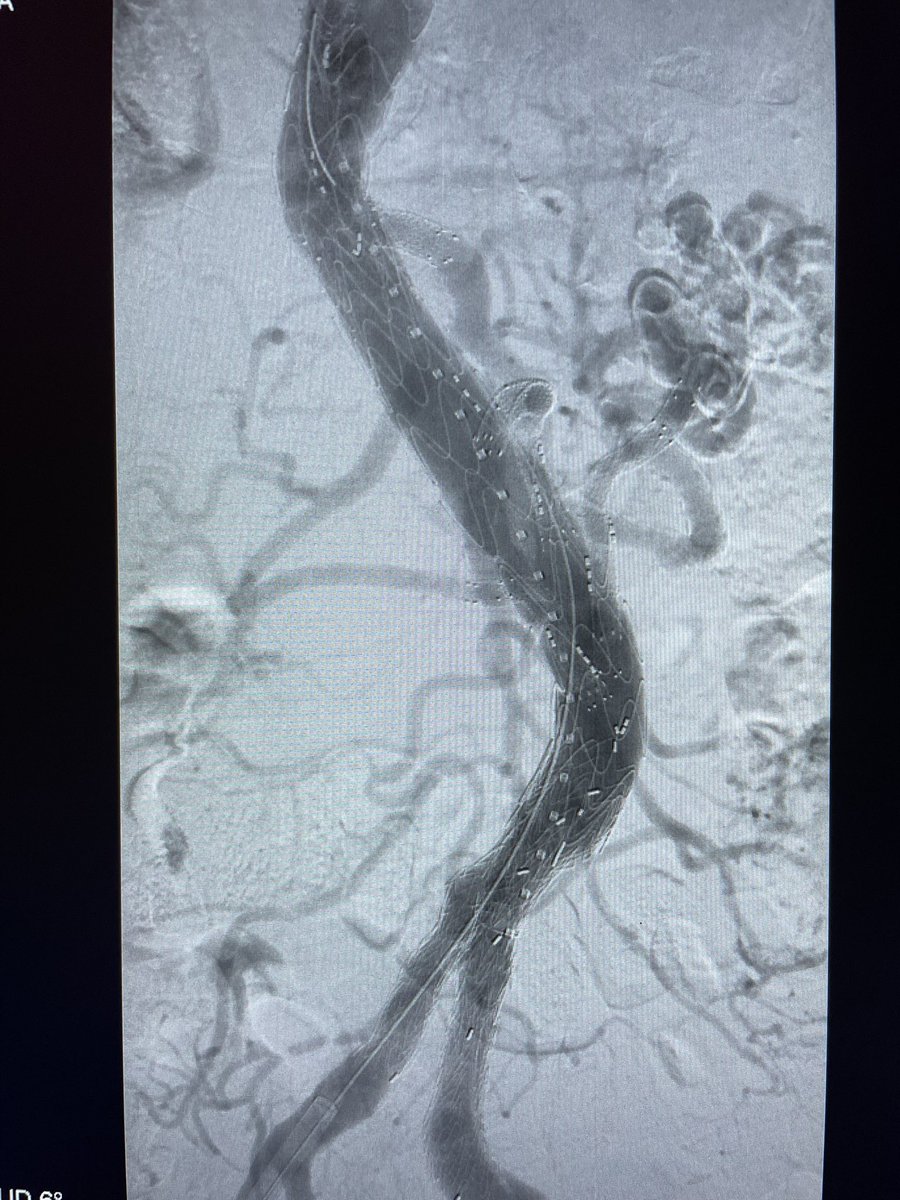

Elderly #CLI pt, unsuccessful antegrade and retrograde approaches. Too diseased for re-entry device to cross. CART technique useful to create fenestration between two planes, allowing re-entry. Palpable DP! Sally Schonefeld FutureVascSurgeons Cedars-Sinai Division of Vascular Surgery